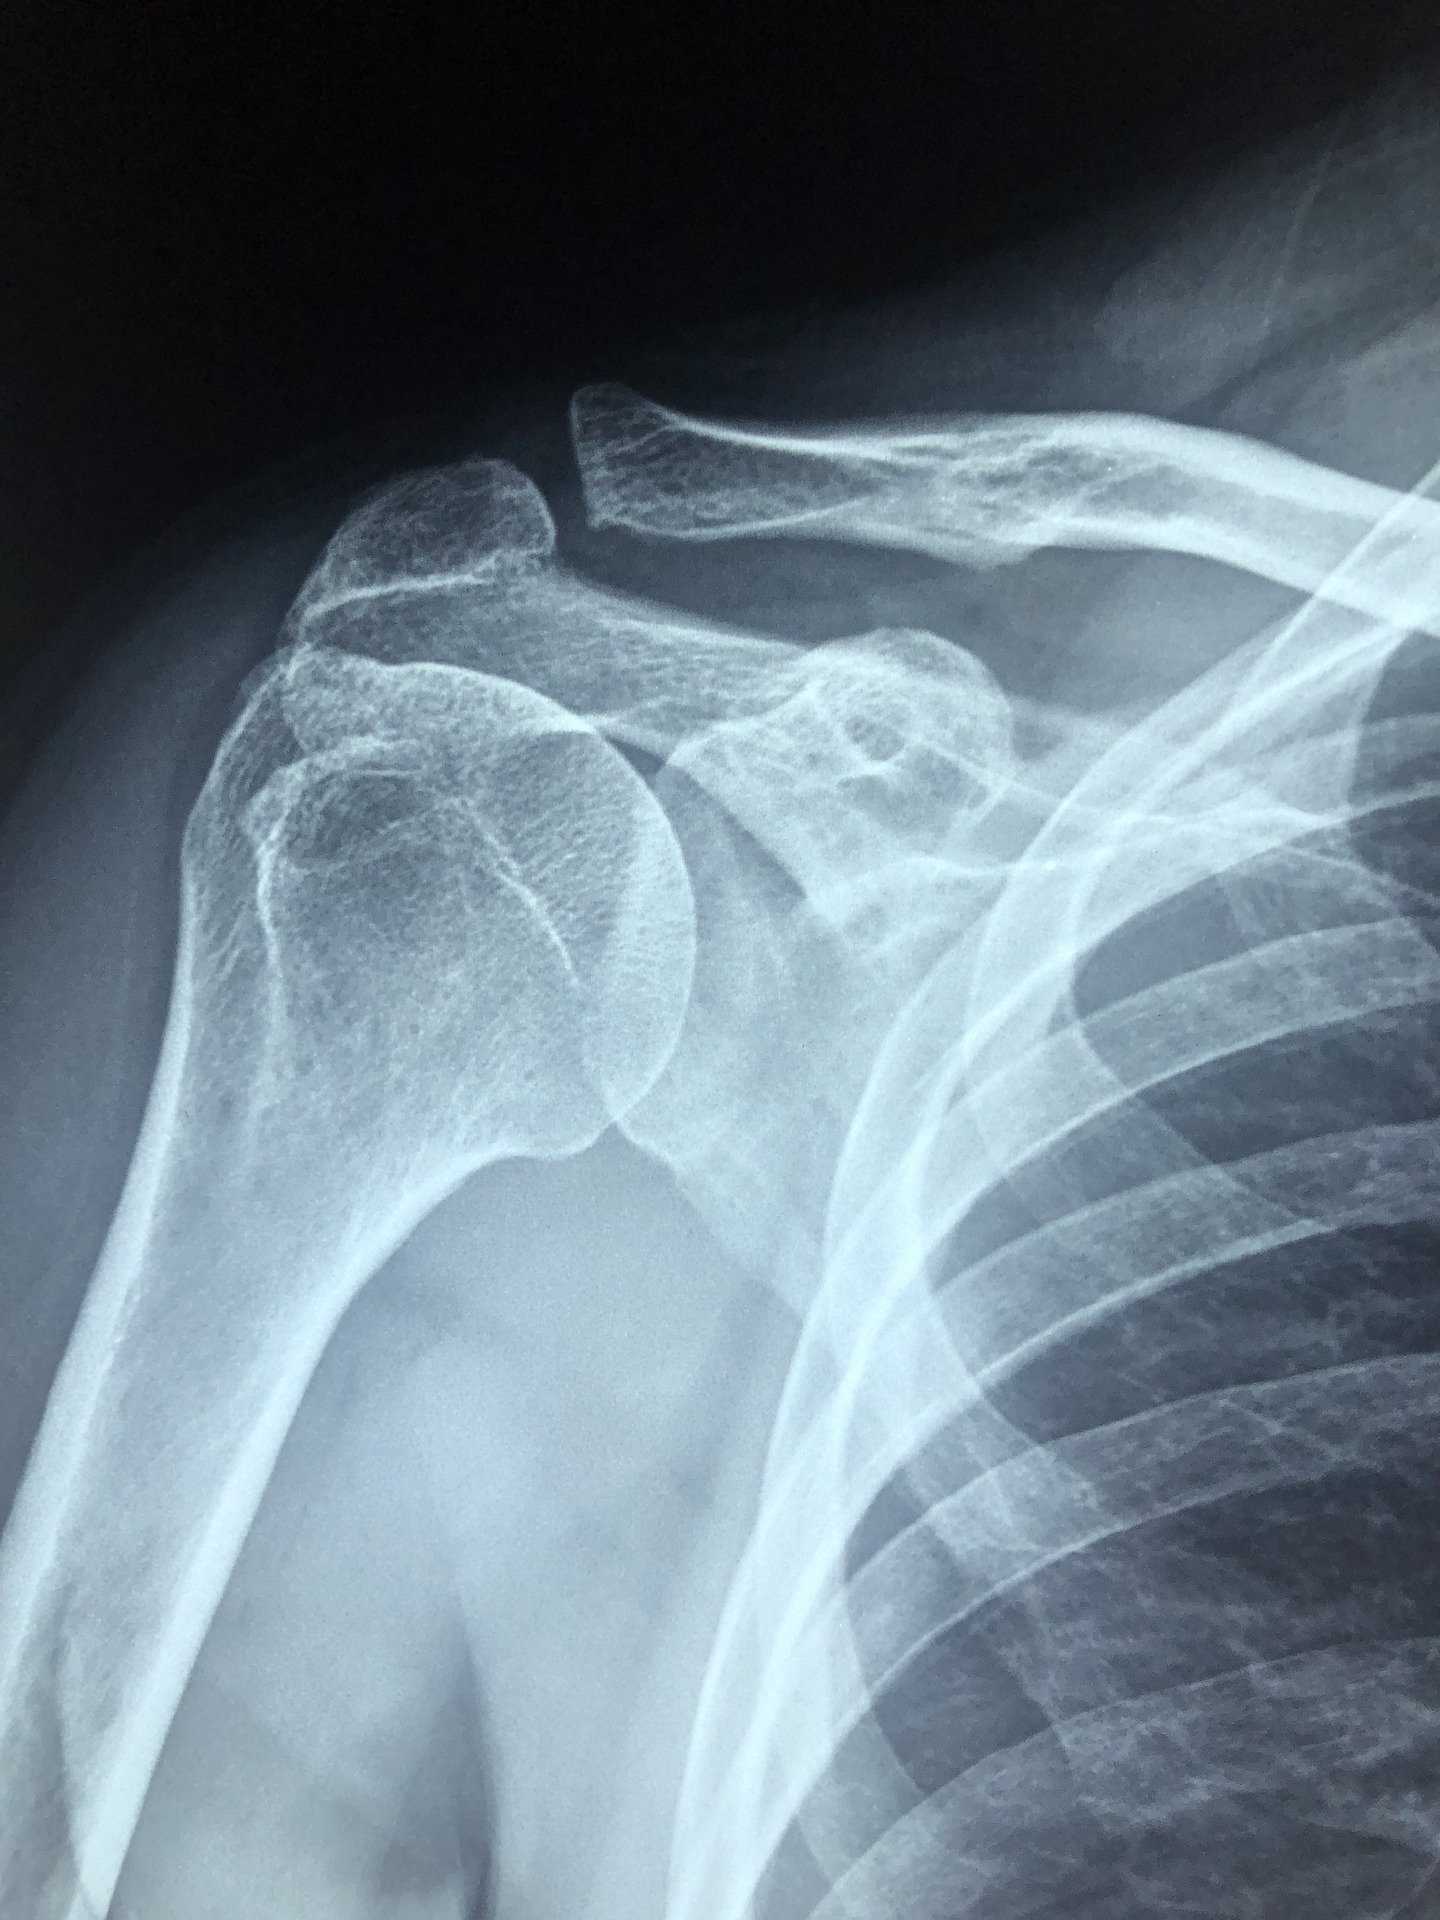

- 초기에는 이학적 검사에 큰 이상이 없으며 X-ray나 초음파 등의 방사선 검사에서도 별다른 이상이 발견되지 않으나

병이 진행될수록 이학적 검사상 관절의 운동범위 제한 등이 나타나 유착성 관절낭염(오십견/동결견)을 의심할 수 있다.

- 단순 방사선 검사는 유착성 관절낭염(오십견/동결견)을 진단하기보다 다른 이상이 있는지 확인하기 위해 시행하며

MRI를 통해 관절낭의 부피 감소, 회전근개 손상의 동반 여부 등 확인할 수 있다.